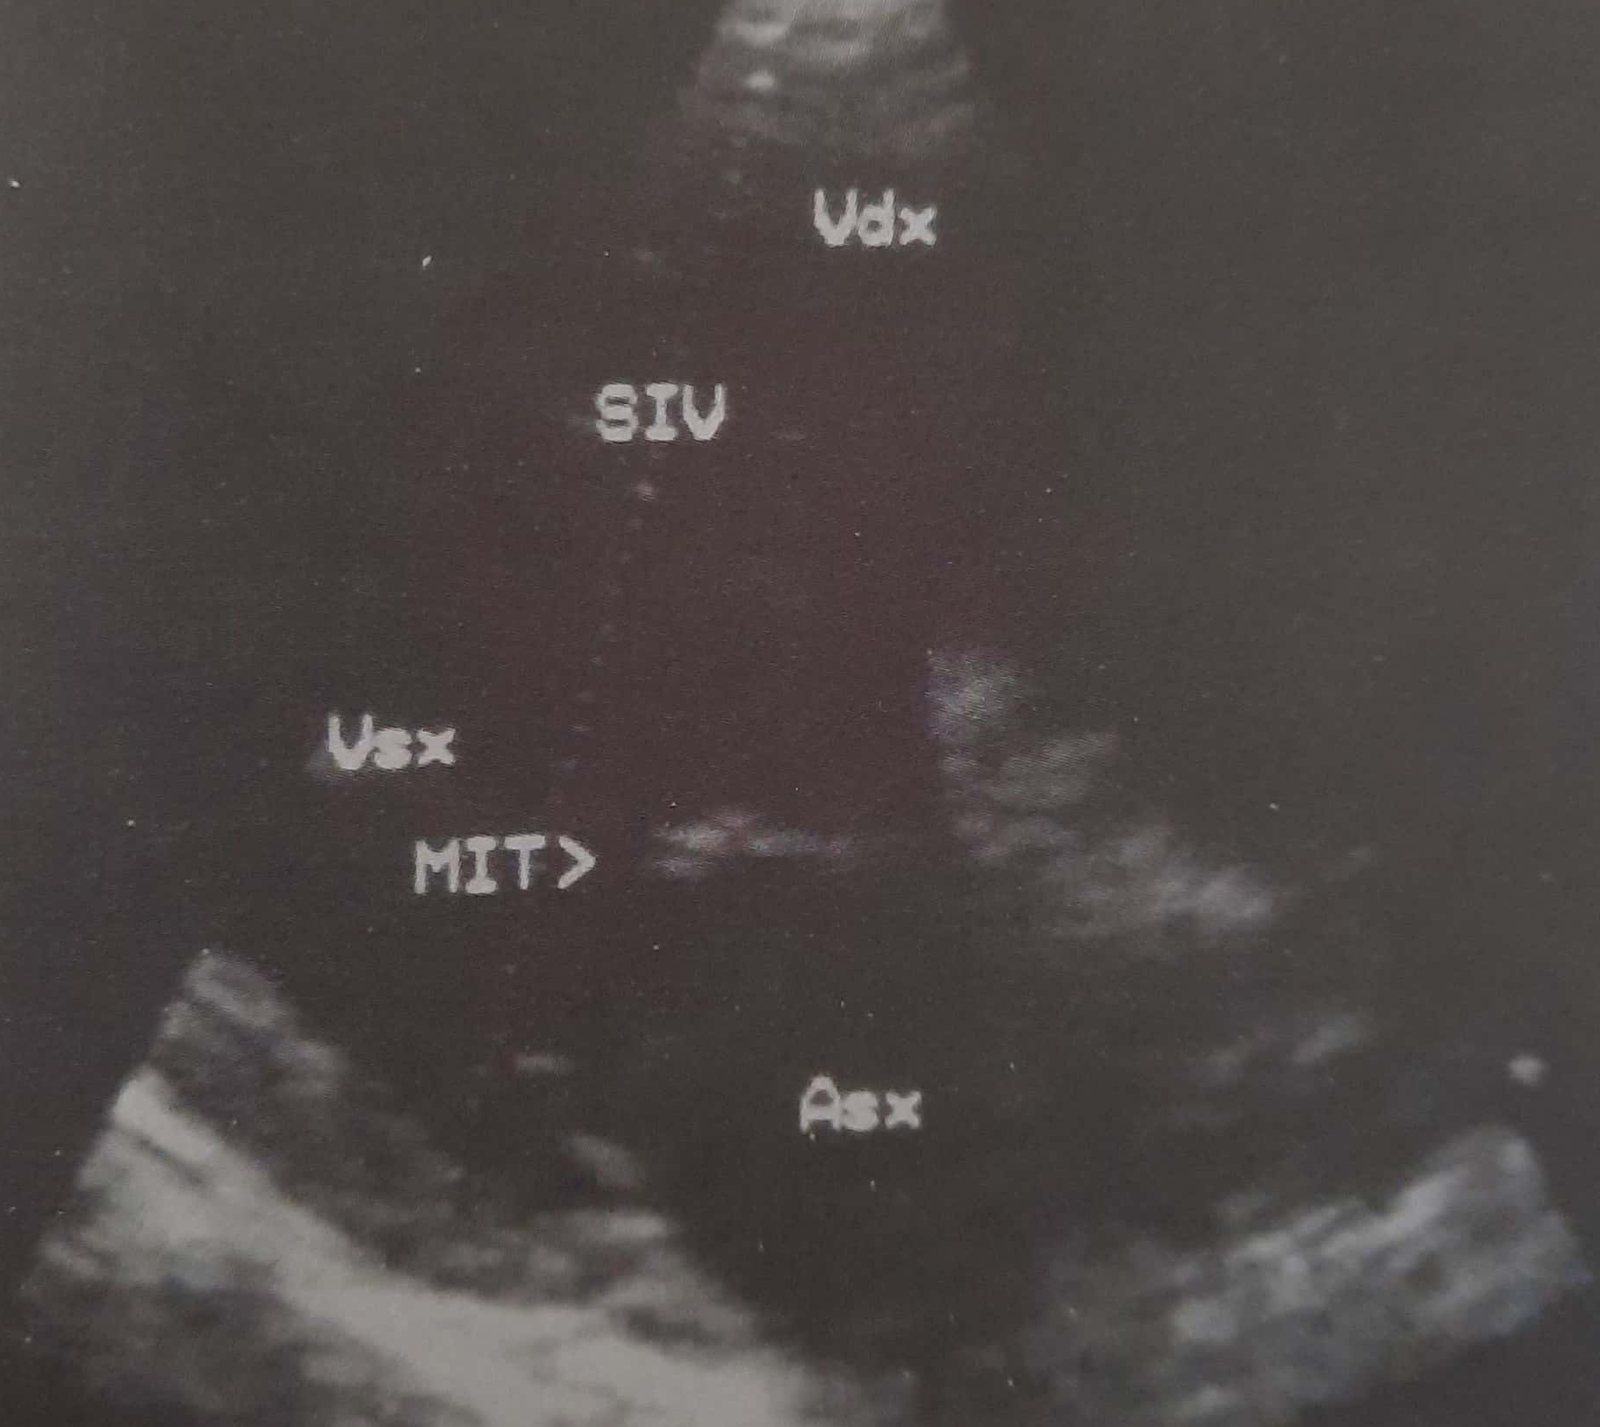

Plani i skanimit korrespondon me aksin gjatësor të organit (djathtas). Baza e zemrës është poshtë djathtas, apex lart majtas. Ky seksion vlerëson ekografinë e valvulës mitrale. Asx = atriumi i majtë; MIT = valvula mitrale; SIV = septum interventrikular; Vdx = ventrikuli i djathtë; Vsx = ventrikuli i majtë.